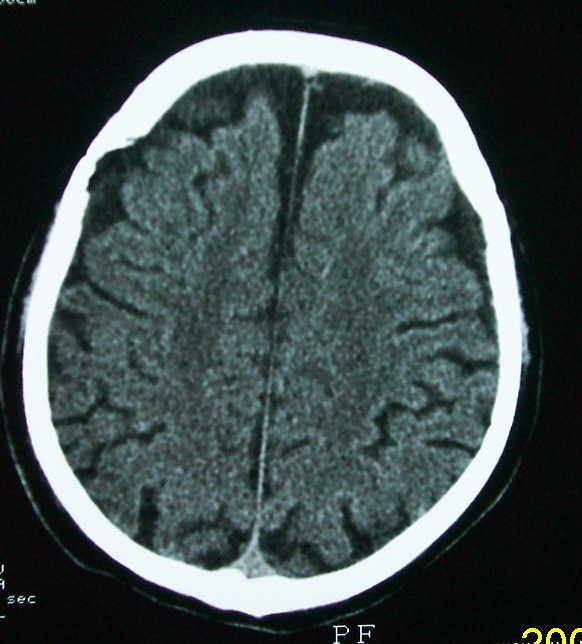

以下是引用余辉在2009-4-15 20:49:00的发言:[br]右侧病灶发生于冠状缝区,但额骨左侧鳞也有病灶,病灶区脑沟裂增宽(有脑萎缩征像,把这个征像放在颅骨病变一起考虑可能有点牵强),是否可能是板障血管畸形所致谢?抑或是嗜酸性肉芽肿或蛛网膜粒压迹那类东西?

以下是引用whzht在2009-4-15 20:57:00的发言:[br]1、额骨改变,考虑蛛网膜粒压迹;[br]2、脑萎缩。